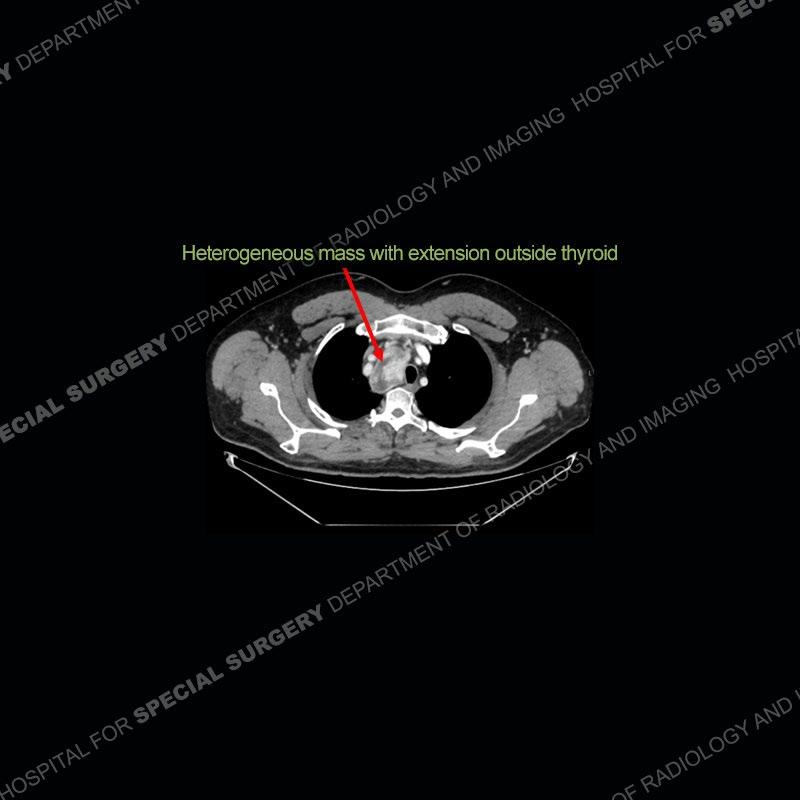

The chest radiographs demonstrate a leftward deviation of the trachea. CT images demonstrate a large, somewhat heterogeneous mass of the thyroid that extends outside the confines of the thyroid tissue. There is a subtle, enhancing soft tissue mass of the proximal right humerus. Slightly prominent mediastinal lymph nodes are present with additionally, multiple supraclavicular lymph nodes.

Over the years we have shown a couple of these cases which may be considered more so an “eye test” then anything else. In clinical practice, these are often very difficult cases as the initial finding of the tracheal deviation may be easily overlooked. Screening radiographs are clearly most often used to assess cardiopulmonary function before induction of anesthesia but at times other findings of great and unfortunately grave consequence can be found. The evaluation of the incidental thyroid mass on CT and MRI is an ever changing situation. Parameters such as age of patient, extension outside of the thyroid, enhancing nodules, and local invasion of lymph nodes are evaluated to see if a lesion needs to be further evaluated.

Although not strictly a part of the evaluation of an “incidental” thyroid lesion, evaluation of the adjacent lymph nodes and bony structures can also be quite important. In this case, there is an enhancing mass of the right humerus. This is very subtle and can only really be recognized by evaluating the density of the bone. Typicaly marrow will have a fatty density or nearly fluid density. As the density, as in this case, approaches soft tissue an infiltrative process must be entertained. Thyroid mets are markedly vascular accounting for the areas of enhancement of the humeral mass. The mediastinal and supraclavicular lymph nodes although not individually enlarged, should raise suspicion of an underlying inflammatory/neoplastic process.